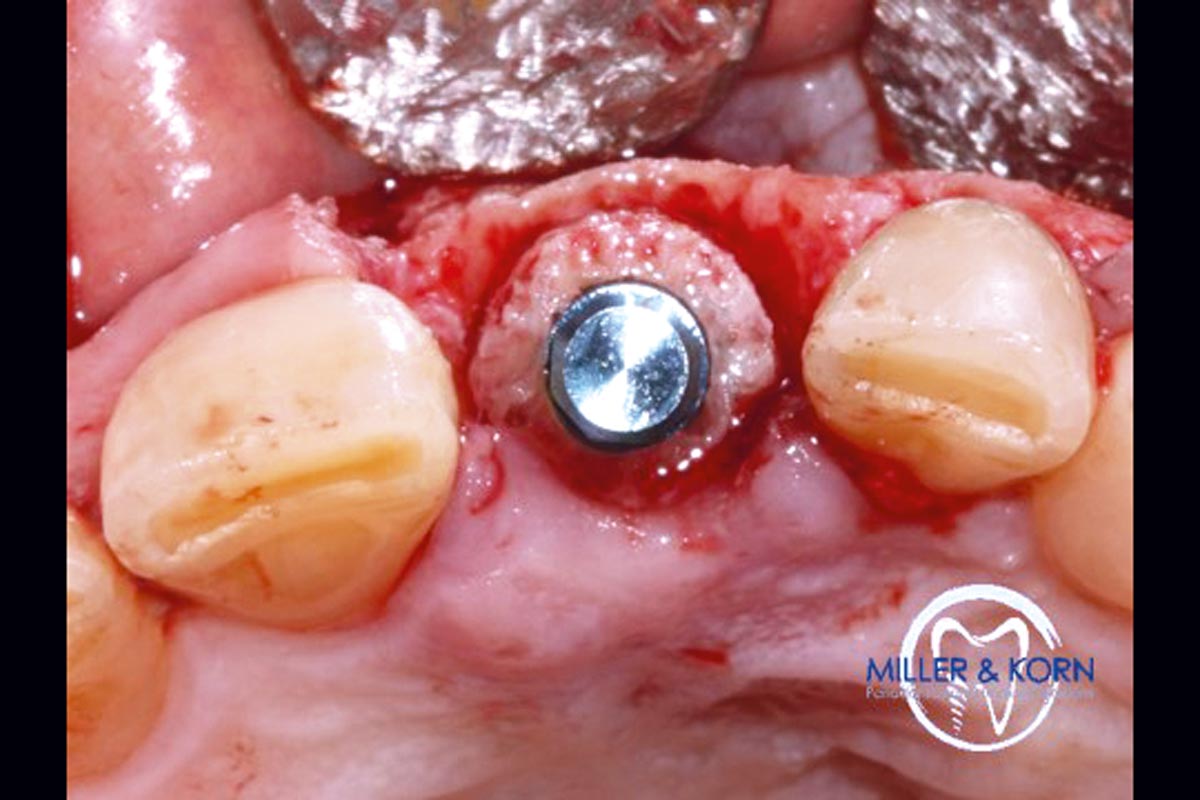

19/39 - Immediate implant insertion through the bone ringImmediate implant placement and correction of horizontal and vertical bone loss using an allograft bone ring, cerabone® and Jason® membrane - Drs. Miller and Korn